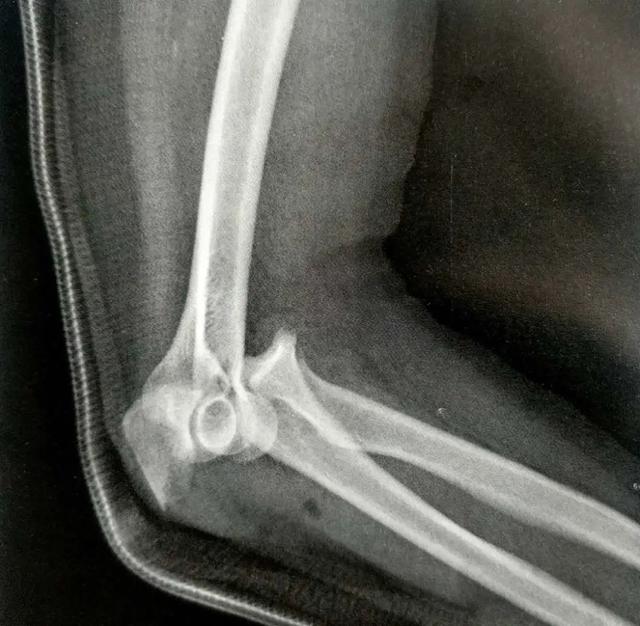

A:鹰嘴的骨折脱位

B-C:用低切迹钢板固定

生物力学测试发现,在横行骨折中,钢板明显比张力带更能提供压缩应力。重建钢板和1/3管型也取得了一些成功,但我们不推荐使用。伤口并发症是使用钢板时最需要关心的问题,因为尺骨近端的软组织覆盖欠佳,以及肘关节屈曲时后侧软组织存在张力。